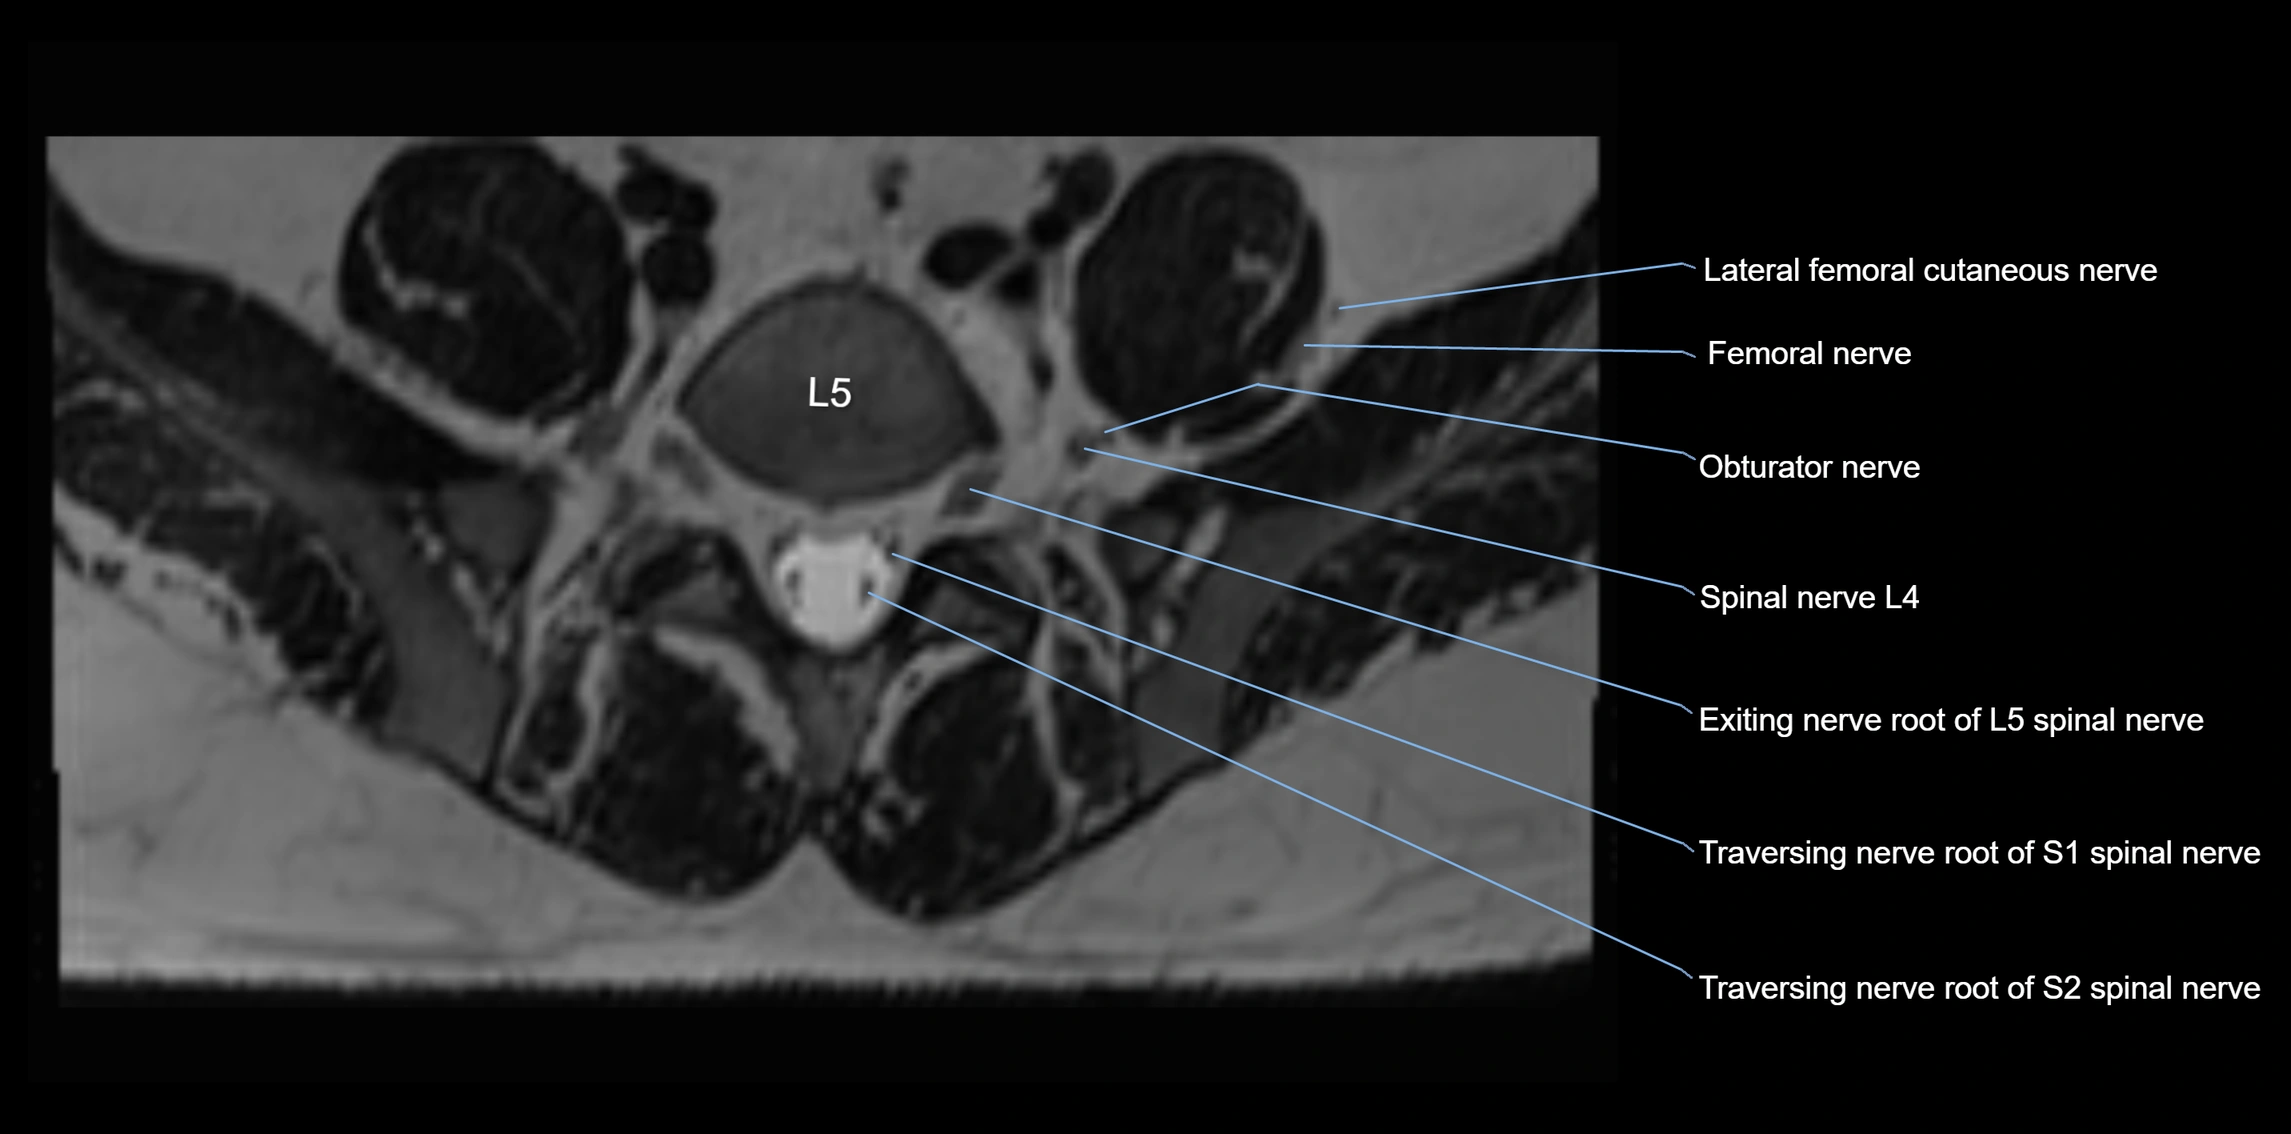

MRI Appearance

T1-weighted images:

• Nerve appears as a very thin low-to-intermediate signal intensity structure

• Surrounded by bright fat, aiding visualization

T2-weighted images:

• Nerve shows intermediate to mildly hyperintense signal compared to muscle

• Pathological involvement appears brighter

STIR (Short Tau Inversion Recovery):

• Normal nerve appears dark

• Inflamed or entrapped nerve appears bright hyperintense

T1 Fat-Sat Post-Contrast:

• Normal nerve enhances minimally

• Pathologic nerve (neuritis, entrapment, tumor infiltration) shows focal or diffuse enhancement

3D T2 SPACE / CISS:

• Nerve appears intermediate to mildly hyperintense compared to muscle

• Surrounded by bright fat or CSF, improving visualization

• Best sequence for mapping small pelvic nerves such as the anococcygeal